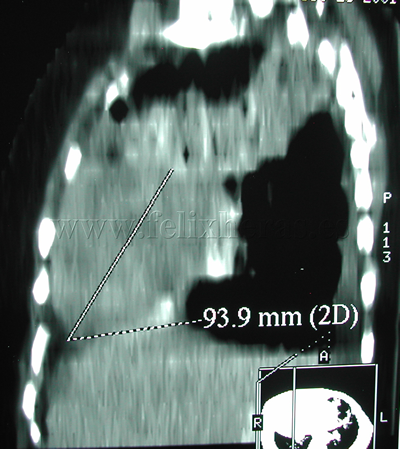

Mesotelioma fibroso pleural